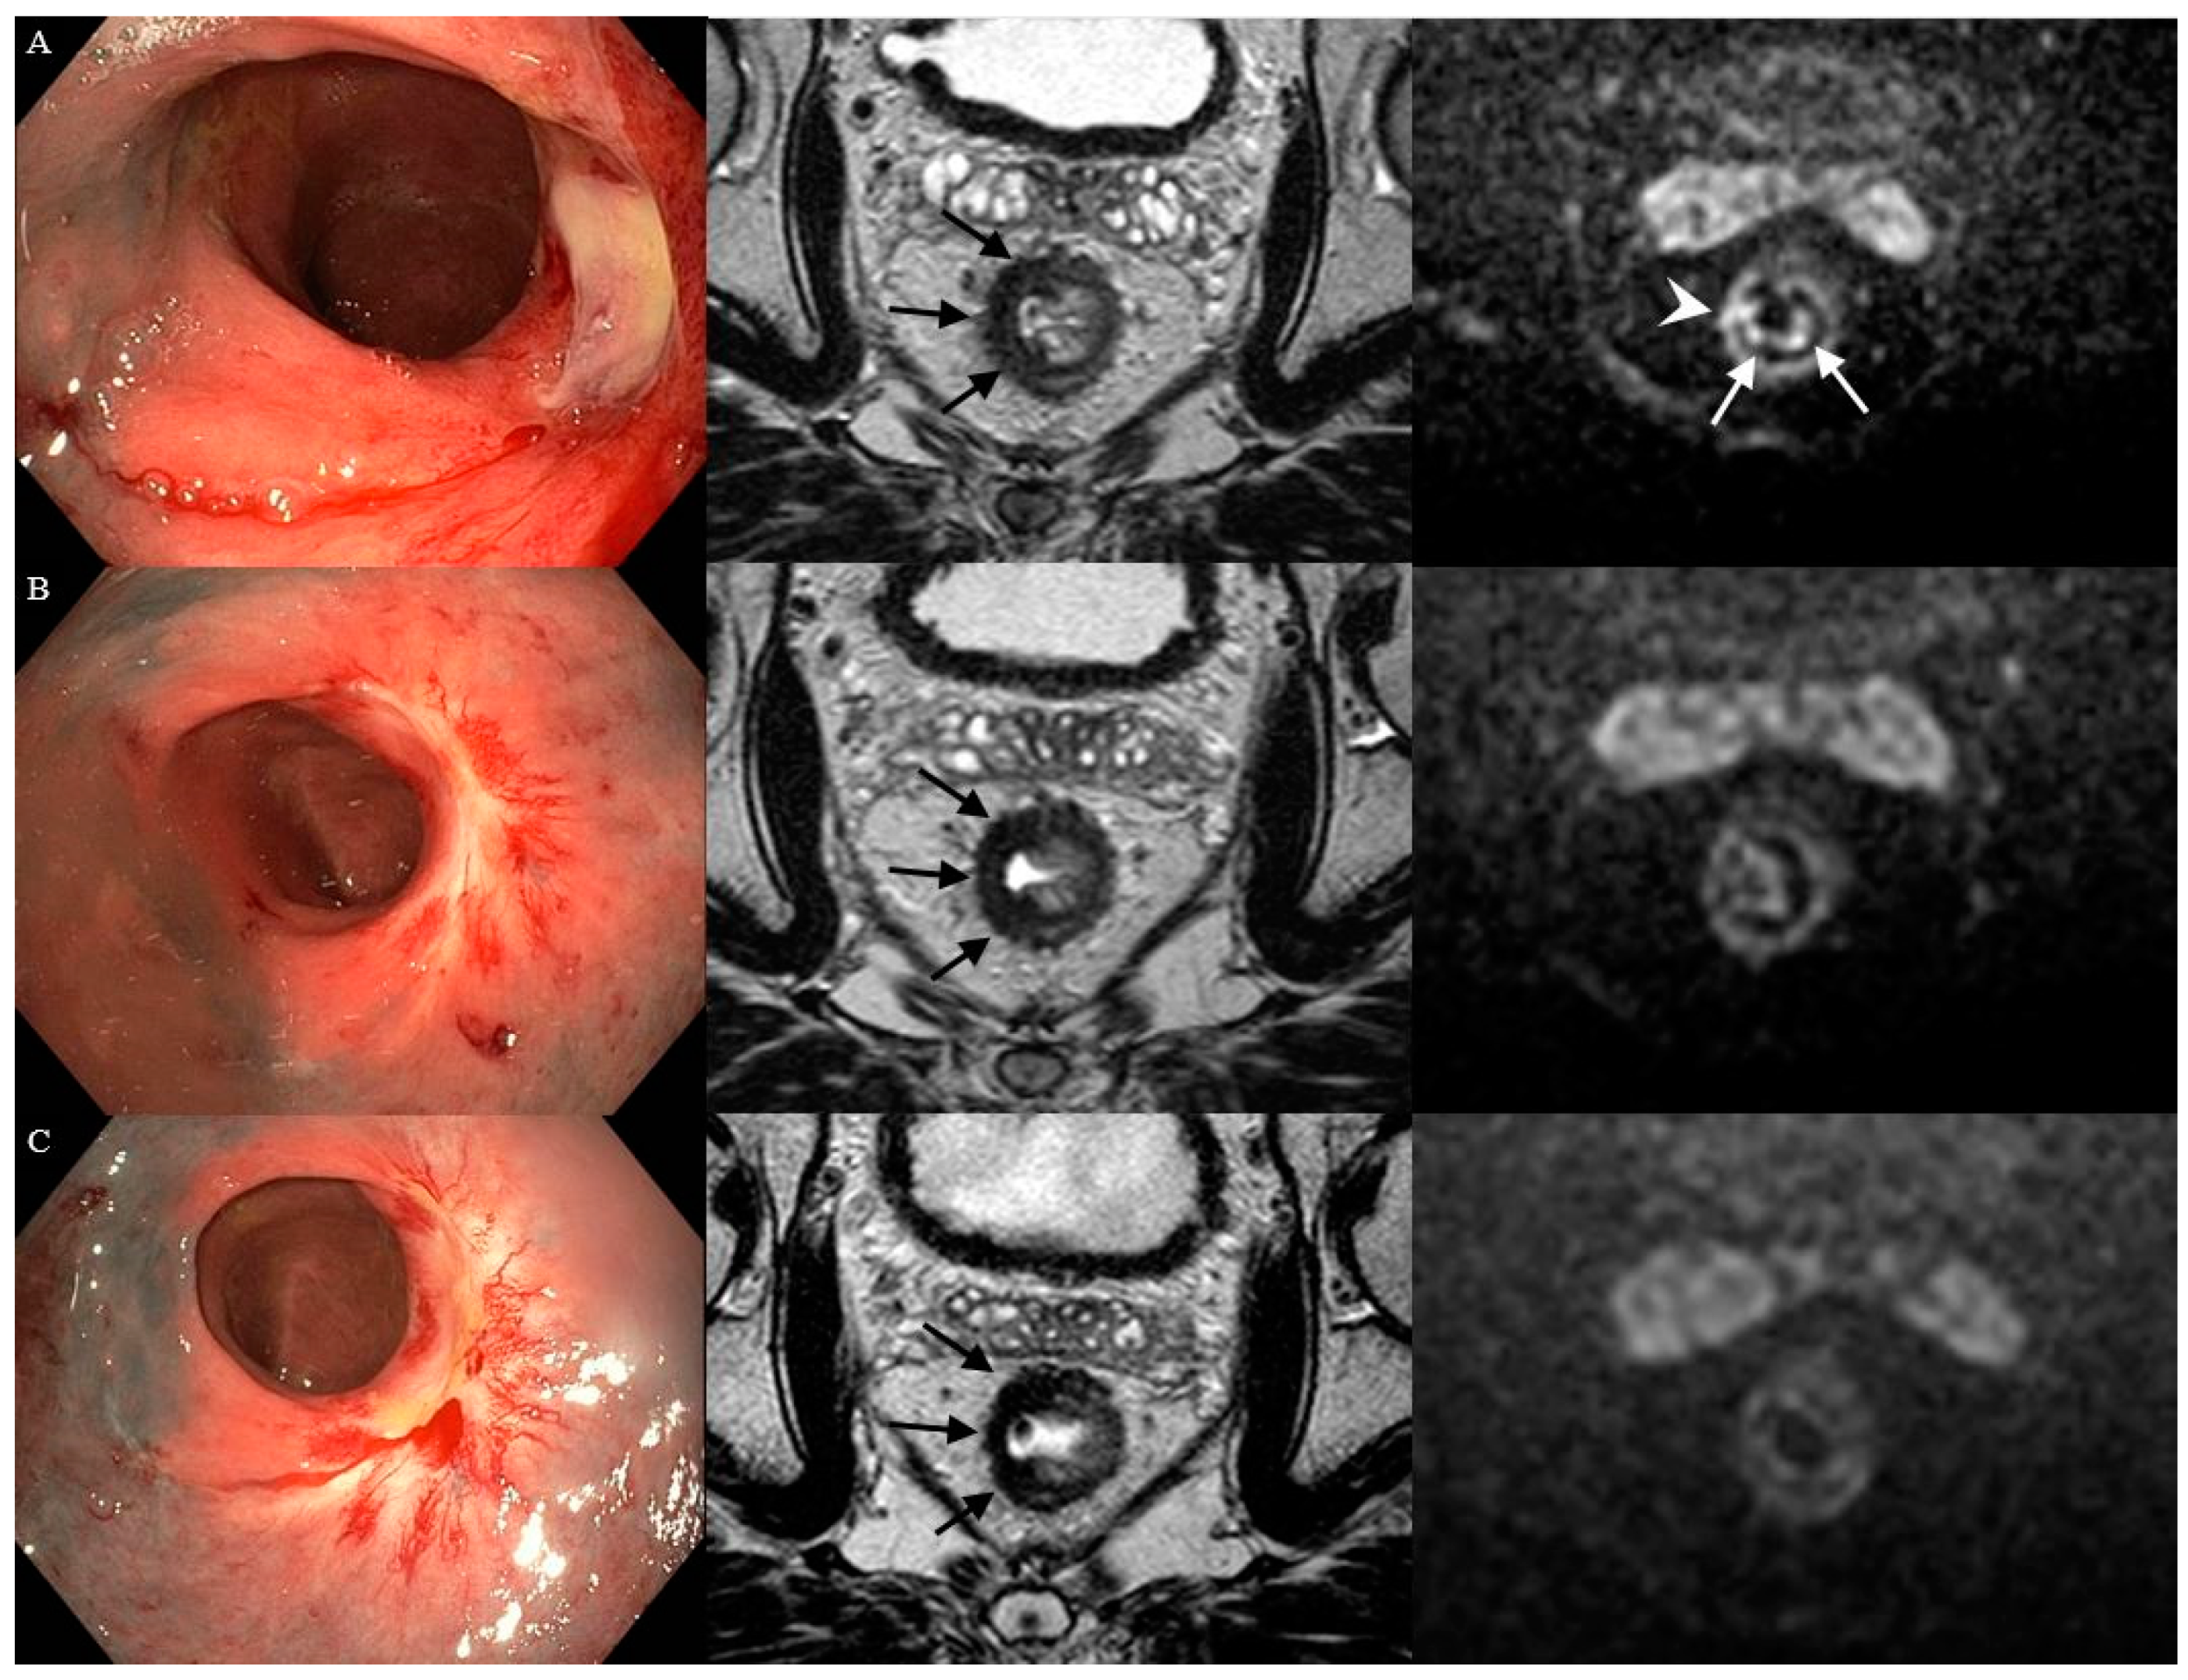

3.1. Features on Endoscopy

3.2. Features on T2W-MRI

3.3. Features on DWI